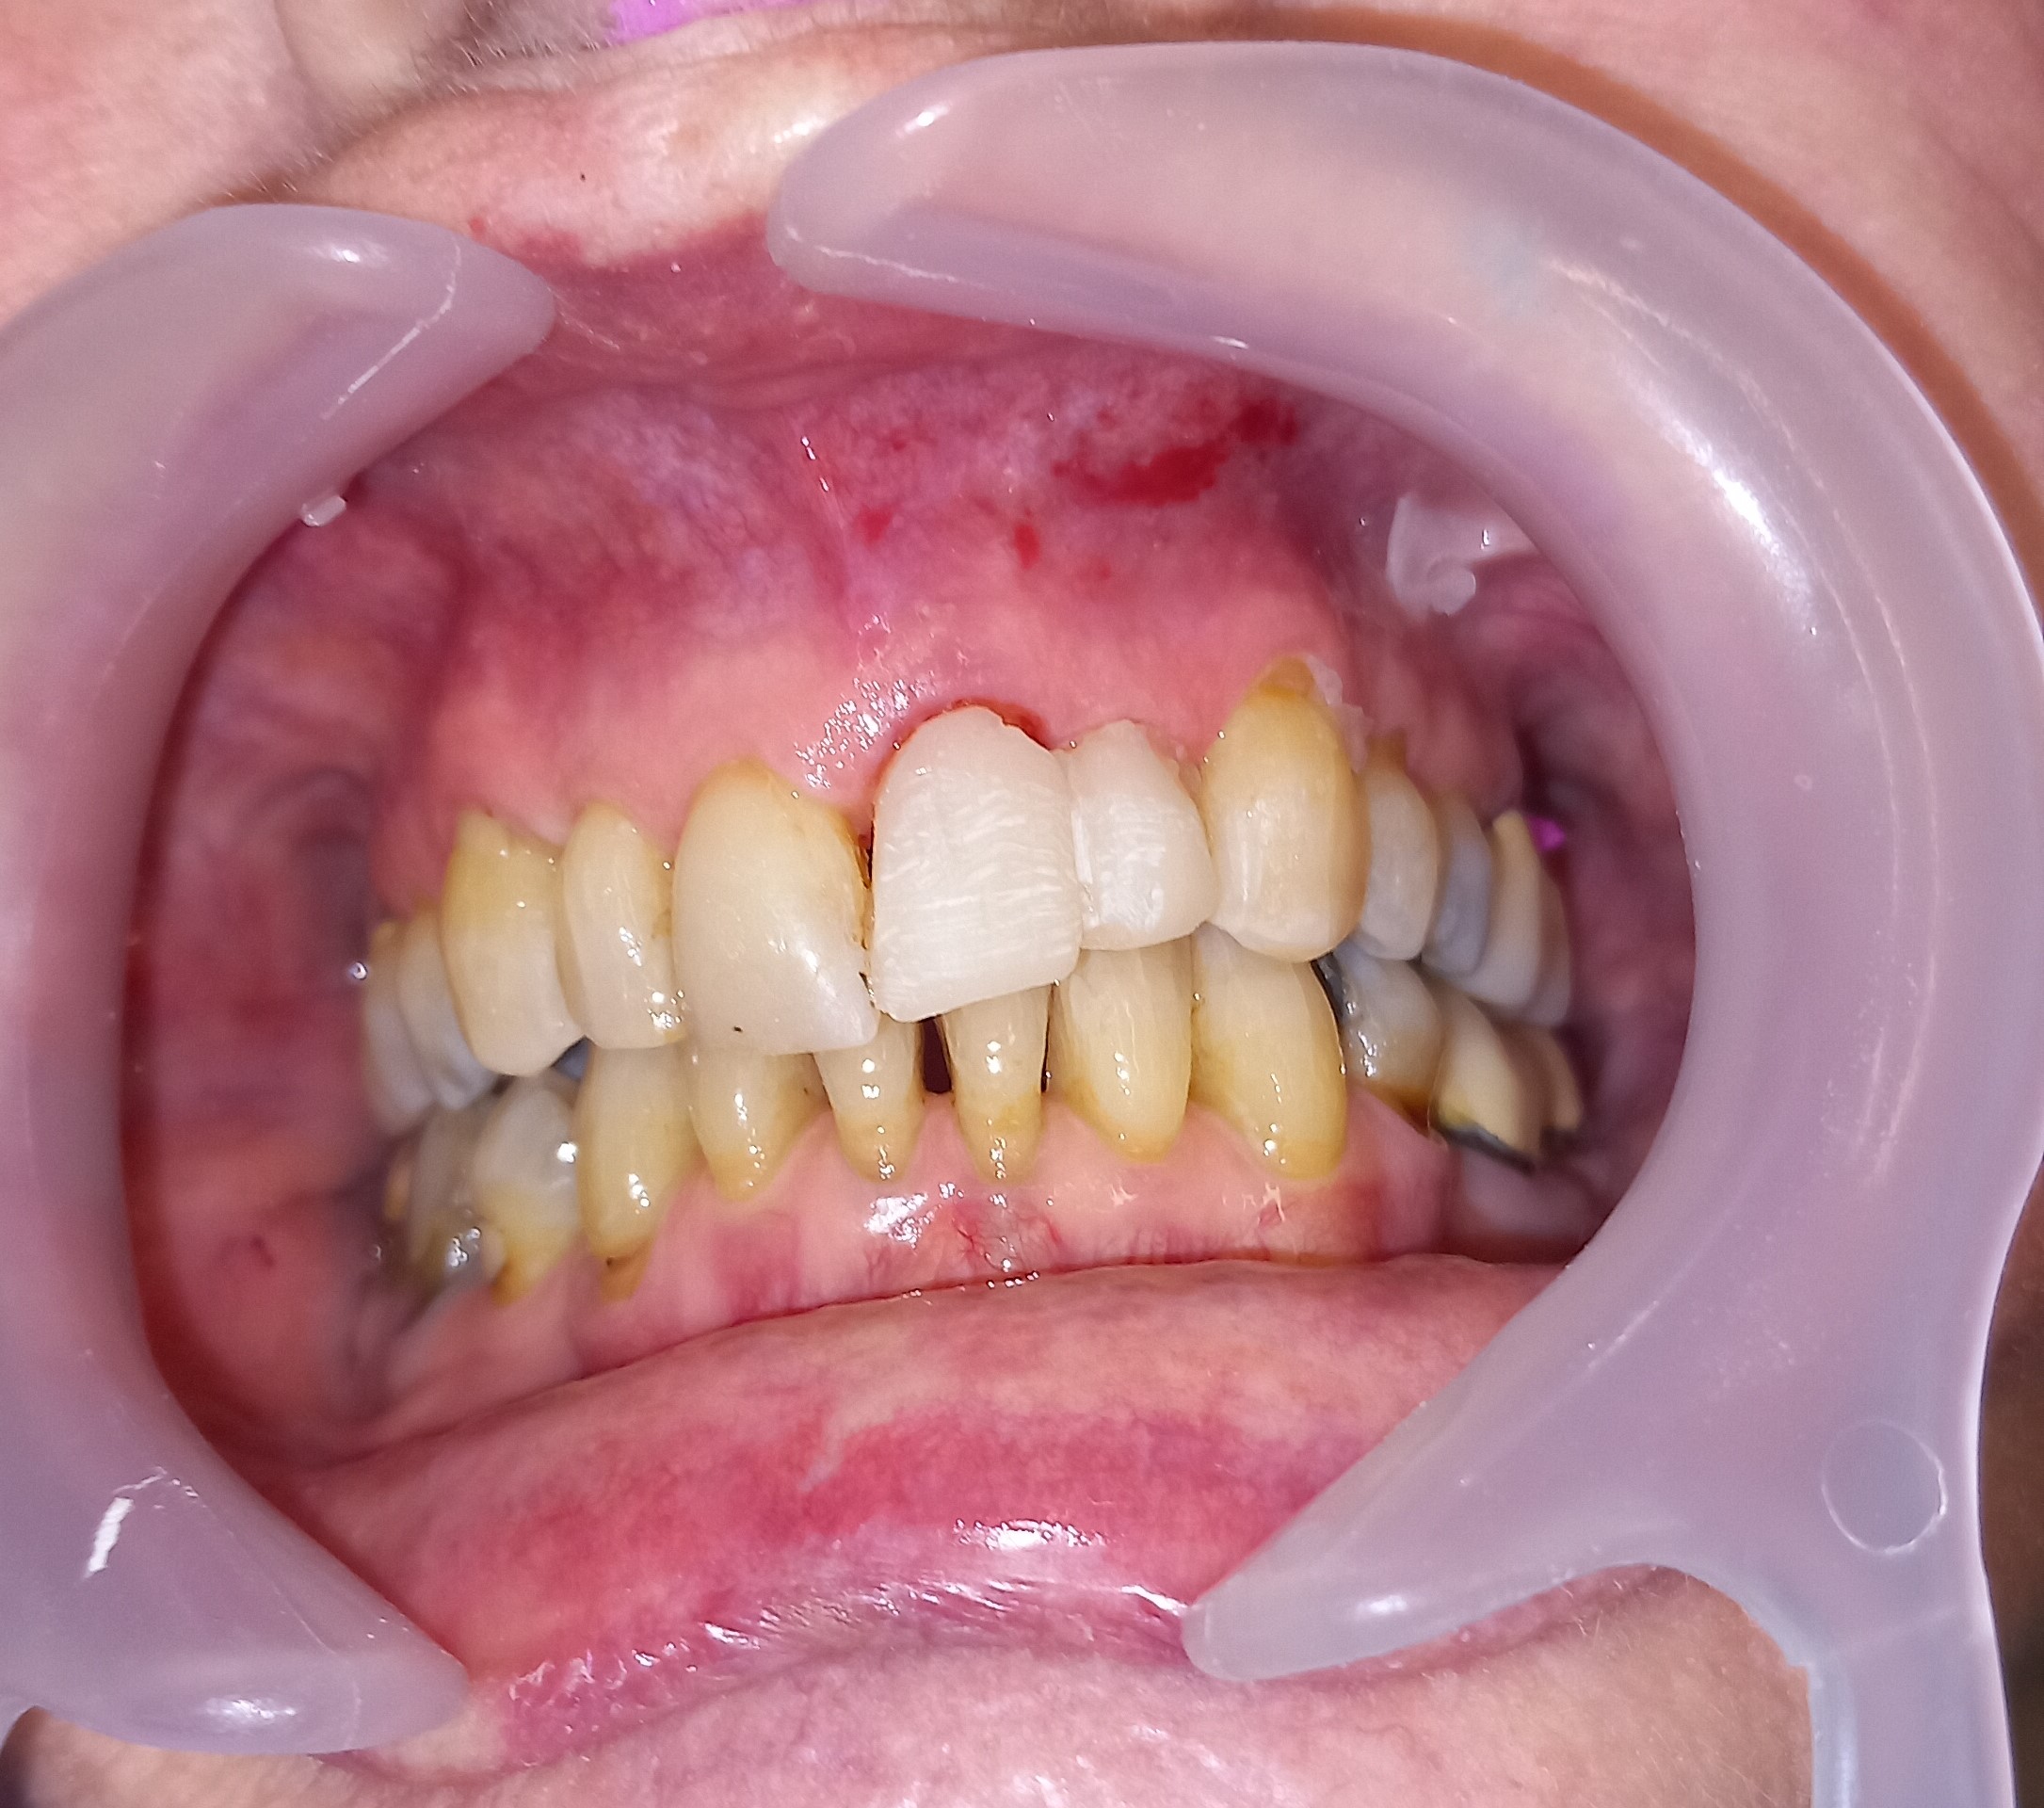

Ο ασθενής είχε πάρα πολλά χρόνια να επισκεφτεί τον οδοντίατρο. Πρόκειται για ένα απαιτητικό περιστατικό, κατά το οποίο ο ασθενής ήταν πολύ συνεργάσιμος καθώς ήθελε να αποκτήσει ένα όμορφο και λαμπερό χαμόγελο. Αρχικά εξάχθηκαν όσα δόντια δεν μπορούσαν να διατηρηθούν πλέον στο στόμα του ασθενή. Στη συνέχεια απονευρώθηκαν τα περισσότερα δόντια και ακολούθησαν ανασυστάσεις όλων των δοντιών. Εφόσον είχε αποκατασταθεί η φλεγμονή των ούλων λήφθηκαν αποτυπώματα και στάλθηκαν στον οδοντοτεχνίτη ο οποίος κατασκεύασε ολοκεραμικές θήκες, οι οποίες ήταν ενωμένες μεταξύ τους (ολοκεραμικό πέταλλο). Ο ασθενής φορούσε προσωρινή γέφυρα στο μεσοδιάστημα που χρειάστηκε ο οδοντοτεχνίτης να κατασκευάσει τη μόνιμη προσθετική εργασία.

Ο ασθενής είναι πολύ χαρούμενος με το λειτουργικό και αισθητικό του αποτέλεσμα. Πρέπει να αναφερθεί οτι όσο καιρό ο ασθενής δεν είχε δόντια δυσκολευόταν πολύ στην άρθρωση του λόγου.

ΠΡΙΝ

Ενδιάμεση κατάσταση αφού ολοκληρώθηκαν οι ανασυστάσεις δοντιών

Ολοκεραμικό πέταλο ζιρκονίου

ΜΕΤΑ